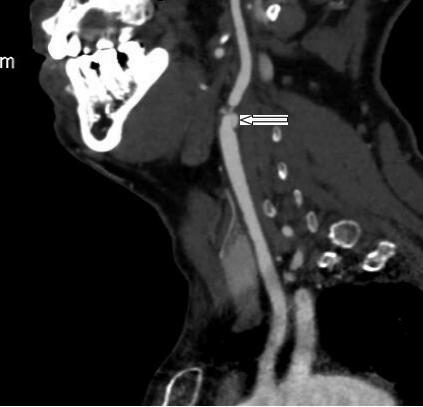

圖1 箭頭所示左頸動脈線樣狹窄

此次行頸動脈內(nèi)膜剝脫手術(shù)的病人是一位67歲的老年患者,因雙側(cè)頸動脈狹窄反復(fù)腦梗困擾15年,此次患者又因頭暈伴視物黑蒙入院,為求手術(shù)治療轉(zhuǎn)來我科。患者高齡,有“高血壓病、糖尿病、肺部感染”等伴發(fā)疾病,患者左側(cè)頸動脈極度狹窄,無法選擇介入手術(shù)。鄭翼德主任帶領(lǐng)的血管外科團(tuán)隊,術(shù)前仔細(xì)評估病情、縝密設(shè)計手術(shù),做好各種應(yīng)急準(zhǔn)備,于2016.04.06成功對患者實施了左側(cè)頸動脈內(nèi)膜剝脫術(shù),術(shù)后患者頭暈、黑蒙、視物旋轉(zhuǎn)等癥狀消失,未出現(xiàn)心腦血管卒中等嚴(yán)重并發(fā)癥,病人臉上重現(xiàn)久違的笑容。